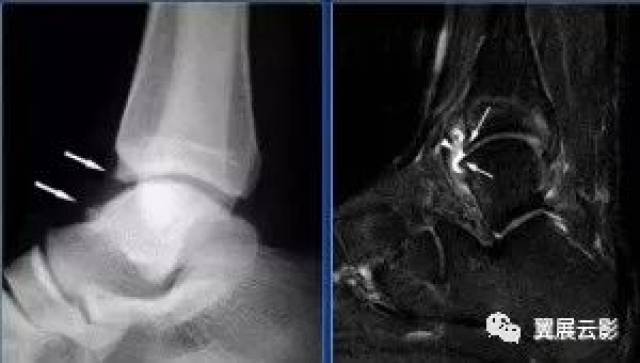

足跟骨刺x光片,足跟骨刺图片

x光片上可见关节或骨的边缘刺状的突起"骨刺"因而得名.

Ⅰ度:滑膜撞击,x线片显示有炎性反应,骨刺大小为3mmⅢ度:严重的外

踝关节x光片